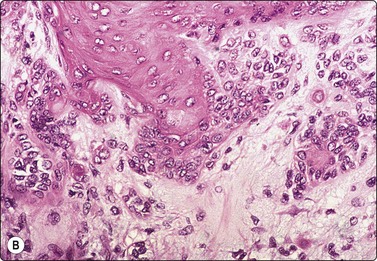

image

Fig. 4.6 Squamous cell carcinoma

Mainly poorly differentiated malignant cells with large vesicular nuclei and large nucleoli; a few squamous and keratinized cells. FNB smears of cervical lymph node metastasis from squamous carcinoma of larynx (A, MGG; B, Pap, HP).

Basaloid squamous carcinoma (Fig. 4.7) is a rare distinct variant of squamous cell carcinoma of the head and neck, which is clinically aggressive and has a predilection for the hypopharynx and the tongue. The smear findings are of squamous cell carcinoma without specific features, but a predominance of basal cells may make the distinction from the solid variant of adenoid cystic carcinoma difficult.43

Fig. 4.7 Basaloid squamous cell carcinoma of head and neck

(A) Poorly differentiated cells with squamous features (MGG, HP; (B) Tissue section mimicking adenoid cystic carcinoma (H&E, IP).